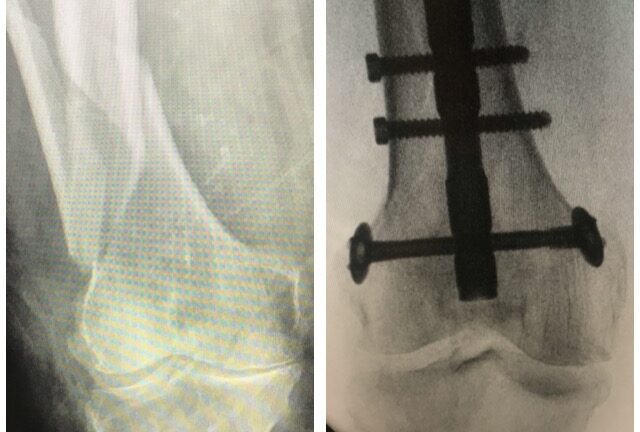

Nilkkamurtuma

Ennen – jälkeen